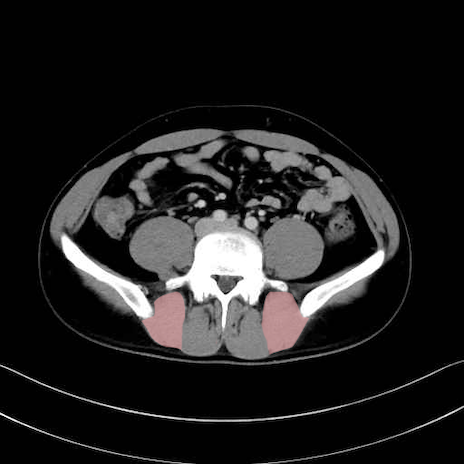

内閉鎖筋 (Obturator internus)